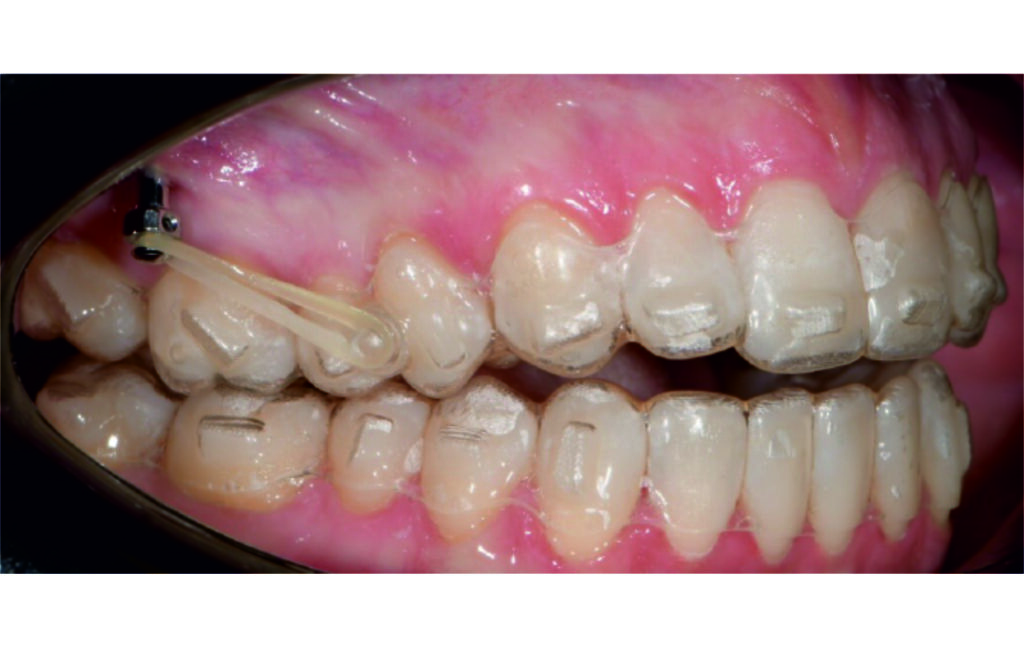

Treatment progress

Vertical vector of elastic traction on buttons and IZC helped with the open bite correction.

No sequential distalization for Class II tendency correction was performed due to skeletal anchorage. Lingual attachments were used to improve aligner grip and control tooth movement, as small, angulated lower incisors are difficult to move due to limited anatomy.

An infrazygomatic crest (IZC) screw with force applied between the upper premolars produces a clockwise rotation of the maxillary occlusal plane. This movement aids in closing the anterior open bite and improves upper incisor display. IZC screws with elastics also enable planned intrusion of the upper molars by 1 mm. Because mandibular derotation after upper posterior correction is difficult to predict, anterior distalization and midline correction were performed in the later stages of treatment.